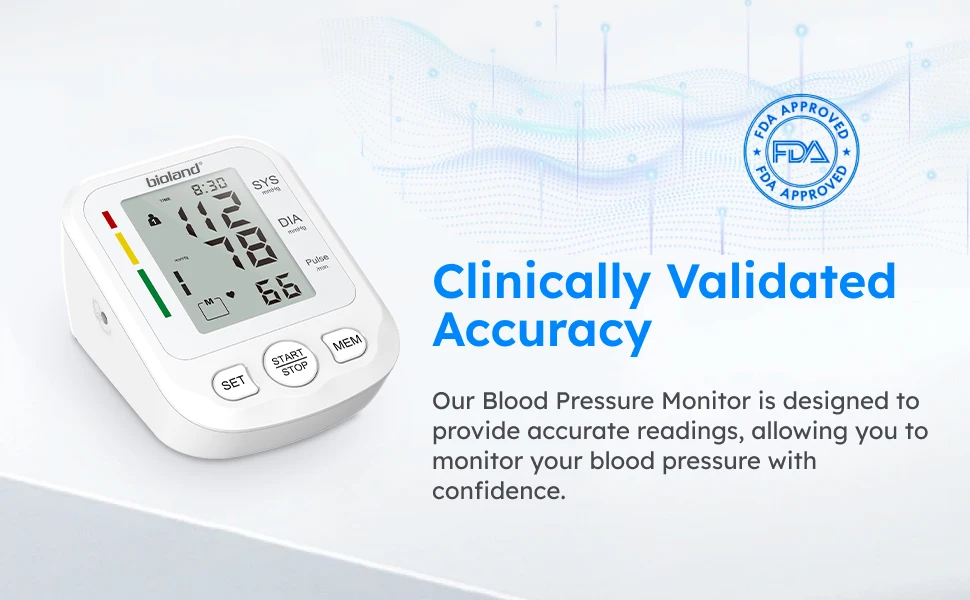

【Safe and reliable】

Boasting specific algorithms & chip, each individually-tested Bioland BP Monitor will provide you with the most trustworthy readings, helping you track your health easily at home. A safe and reliable BP-machine to our families.

【Large LED Display】

The large LED display with clear and oversized numbers, makes it easy to read your real-time blood pressure and pulse rate. High precision chip of large LED touch screen provides clinically accurate readings, giving the most exact systolic, diastolic pressure and pulse rate data by one touchable button and easy to read the backlist screen with multi-colored LED indicator lights.

【120 Memory for 2 Users】

This BP unit can monitor 2 users together, store 120 readings with date & time stamps for each displays the average of last 3 readings, includes irregular heartbeat detection. Helps users to easily track their health, blood pressure and heart rate according to the specific time and date.